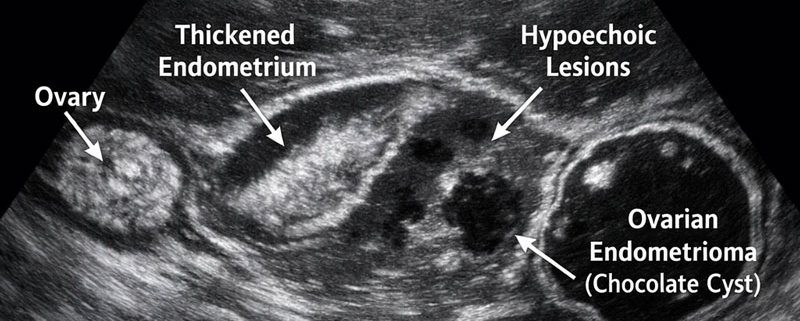

۱. تشخیص کیستهای آندومتریوما (کیست شکلاتی)

یکی از شایعترین نشانههای آندومتریوز، ایجاد کیستهایی در تخمدان است که با خون قدیمی و تیره رنگ پر شدهاند و به همین دلیل به آنها «کیست شکلاتی» میگویند. سونوگرافی آندومتریوز با دقت بسیار بالایی (نزدیک به ۱۰۰ درصد) میتواند این کیستها را شناسایی کرده و اندازه و تعداد آنها را مشخص کند.